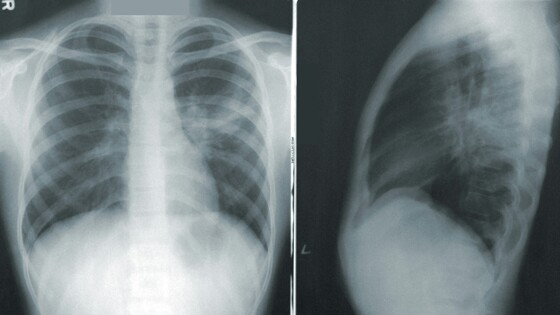

Цель исследования заключается в клинико-экономической оценке использования НДКТ вместо флюорографии для скрининга рака легких у текущих и бывших курильщиков со стажем 30 лет в возрасте 55-79 лет. Низкодозная компьютерная томография создает 3D-картинку легких, что позволяет увидеть даже самые маленькие опухоли, в то время как флюорография выявляет только затемнения в легких, часто не замечая незначительные новообразования.